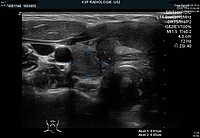

Beim Verdacht auf einen Hyperparathyreoidismus werden in der Regel zwei Untersuchungen durchgeführt:  ein Ultraschall (Bild 1) und eine Szintigrafie (Bild 2) um die vergrösserte Nebenschilddrüse zu lokalisieren und somit die Operation zur Entfernung dieser Nebenschilddrüse zu planen.